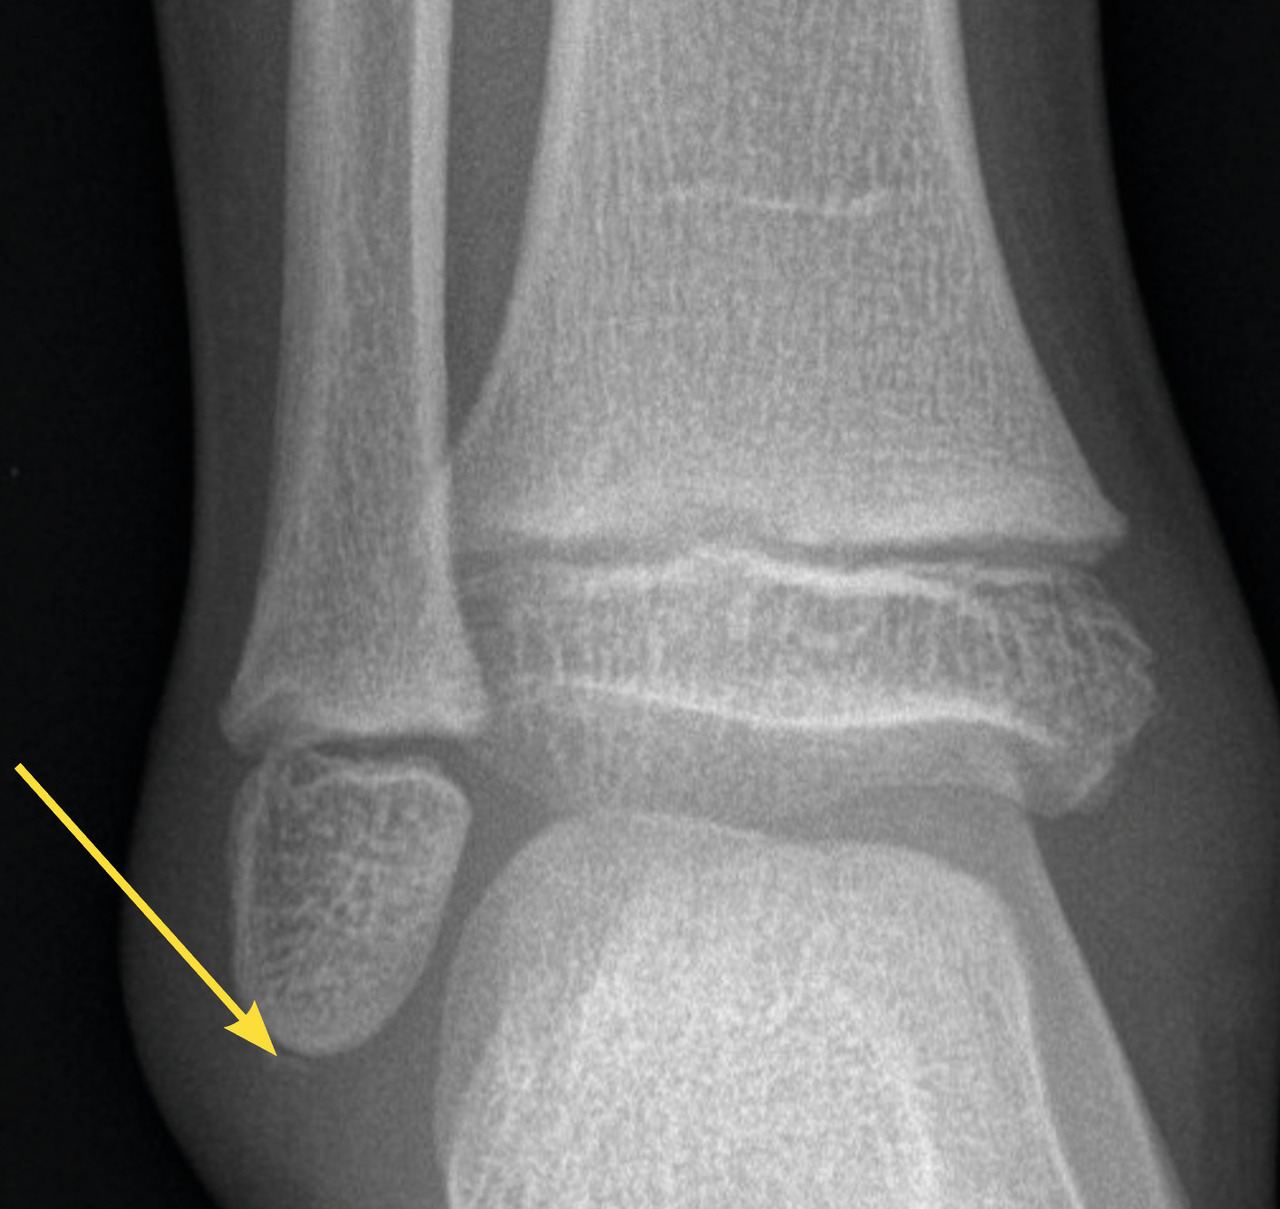

Le diagnostic différentiel est principalement constitué par les fractures. Celles-ci sont spécifiques du fait des particularités de l’os pédiatrique, et le tableau clinique n’est pas toujours aussi flagrant que chez l’adulte. Il n’est pas rare de voir des enfants conserver un appui partiel sur des chevilles fracturées. Dans environ 20 % des traumatismes en inversion, il existe une avulsion de la pointe de la fibula8 (fig. 2), qui doit être recherchée et traitée par une botte en résine durant un mois, quel que soit l’âge. Les décollements épiphysaires de la malléole externe sont beaucoup plus rares que ce qui a longtemps été cru6, et leur pronostic fonctionnel semble bon quel que soit le traitement.

Chez l’enfant de moins de 10 ans qui consulte en urgence avec des signes cliniques nets (œdème, hématome, douleur importante, appui impossible), la radiographie est indispensable à la recherche de signes d’entorse grave, en particulier une avulsion de la pointe de la fibula.

En cas de lésion radiographique (avulsion de la pointe de la fibula), une immobilisation stricte par botte plâtrée est indiquée pour une durée d’un mois.